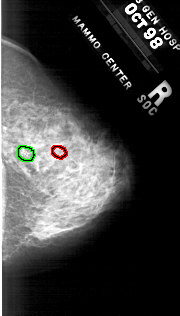

A_1819_1.RIGHT_MLO

RIGHT_MLO LINES 5491 PIXELS_PER_LINE 2506 BITS_PER_PIXEL 12 RESOLUTION 43.5 OVERLAY

FILE: A_1819_1.RIGHT_MLO.OVERLAY

TOTAL_ABNORMALITIES 2

ABNORMALITY 1

LESION_TYPE CALCIFICATION TYPE PLEOMORPHIC DISTRIBUTION CLUSTERED

ASSESSMENT 4

SUBTLETY 4

PATHOLOGY MALIGNANT

ABNORMALITY 2

SUBTLETY 2